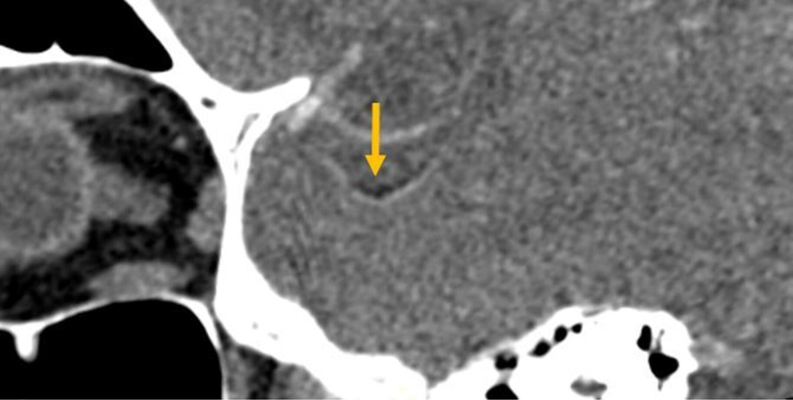

Teaching point: Spectral tomography offers valuable complementary diagnostic tools in the setting of cerebral fat macroembolism, a rare condition often presenting with nonspecific clinical symptoms.

Abstract Image